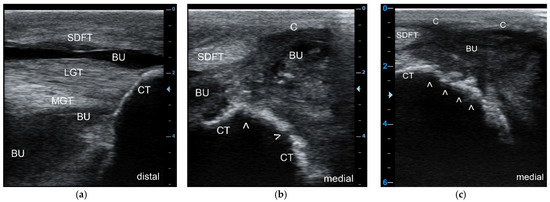

Ultrasonographic examination was conducted in all 29 patients and the following was identified: an inflammatory, heterogenous effusion in all 33 cases of bursitis (100%), gas pockets within the bursal cavity in 15 cases (45.5%), bone lesions at the CT in 16 cases (48.5%) (Figure 2a–c), and lesions of the SDFT with loss of echogenicity and loss of parallel fiber arrangement leading to the diagnosis of partial and total tendon necrosis/rupture in three cases (9.1%), respectively. All three cattle with SDFT lesions had concurrent bone osteolysis of CT.

Figure 2. Longitudinal sonogram (5 MHz linear) of the CT region at the insertion site of the Achilles tendon (a), and transverse sonograms (5 MHz linear) of the plantaromedial (b) and medial aspect (c) of the proximal CT showing a septic purulent bursal effusion (a) and bone involvement (infection) in this cow; the bursal cavity (BU) is highly enlarged due to the presence of heterogeneous hypoechoic exudate with an anechoic, partly hypoechoic to echoic and “snow-flurry-like” appearance, the latter in particular at the medial aspect of the bursal cavity with flow phenomena (b,c), indicative of a purulent exudate. Due to the severe effusion, the superficial digital flexor tendon (SDFT) is displaced plantarily, as is the bursal capsule (C). The contour of the CT appears normal at the insertion site of the lateral (LGT) and medial gastrocnemius tendons (MGT) (a), but highly irregular (white arrows) at the plantaromedial (b) and, in particular, at the medial aspect of the CT (c) indicating extensive osteolysis.